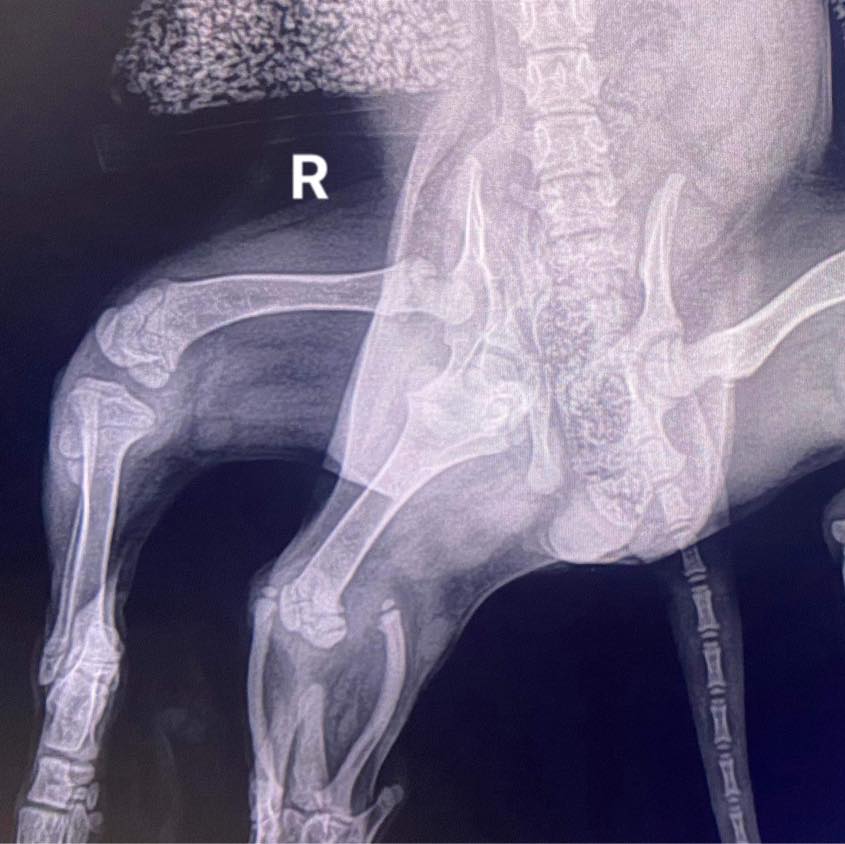

Ariel, ki ima več prirojenih nepravilnosti, so operirali v veterinarski bolnišnici v Somersetu. Odstranili so ji odvečni taci, operacija pa je potekala brez težav, je povedal predstavnik bolnišnice.

Tudi CT-slikanje ni pokazalo nobenih dodatnih nepravilnosti, tako da upajo, da bo psička dobro okrevala.